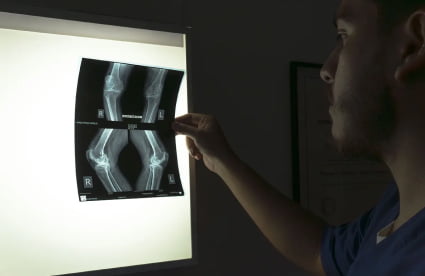

Radiología Corporal

Nuestro servicio de radiología corporal utiliza equipos digitales de rayos X para obtener imágenes detalladas de huesos y tejidos internos, ayudando a diagnosticar fracturas, infecciones y otras condiciones médicas. Contamos con profesionales preocupados por el bienestar de sus pacientes, con amplia experiencia en la toma y lectura de las radiografías permitiendo brindar un diagnóstico confiable y oportuno.